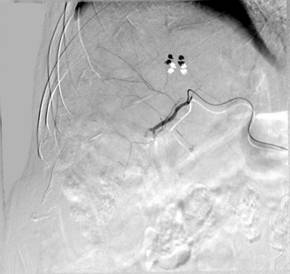

术中造影图片:

栓塞后图片: